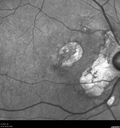

Macular Telangiectasis and Vision loss following vitrectomy with membrane peel421 views76 year old man with MacTel who had membrane peel in the right eye 10 years ago with permanent vision loss.

VA OD: sc20/200-4 and VA OS: sc20/25-1